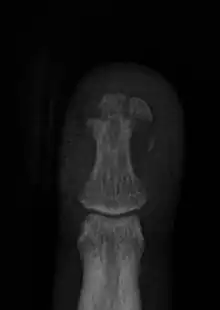

Finger injuries are usually diagnosed with x-ray and can get to be considerably painful. The majority of finger injuries can be dealt with conservative care and splints. However, if the bone presents an abnormal angularity or if it is displaced, one may need surgery and pins to hold the bones in place.